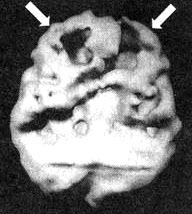

Мозг Кента. СДВ. До и во время приема Adderall

Трехмерное изображение — нижняя поверхность.

В состоянии покоя — обратите внимание на хорошую активность всего мозга.

Во время концентрации: обратите внимание на выраженное снижение активности в префронтальной коре (см. стрелки).